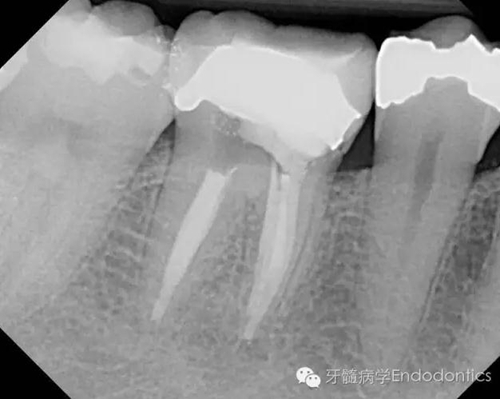

患者因右下第一前磨牙劇烈疼痛、腫脹來診,自訴2年前該牙行根管治療,突發(fā)劇痛。X線示患牙已行根管治療并超填?;佳涝\斷為已行根管治療合并急性根尖周膿腫。一些牙醫(yī)和牙髓病專科可能會直接采取根尖手術(shù)治療患牙,而我認(rèn)為手術(shù)是最終手段,尤其對于該病例。

我決定對患牙行一次性根管再治療。我成功的取出了一根斷針和三根(其中兩根超出根尖)Thermofil(固核載體)。對所有根管進(jìn)行徹底的清理、成形,干燥后使用熱牙膠垂直加壓技術(shù)完成充填。

兩年后復(fù)診,病變愈合。

圖1.術(shù)前X線片(a)

圖2.術(shù)前X線片(b)

圖5.根充后X線片

圖6.隨訪兩年后X線片